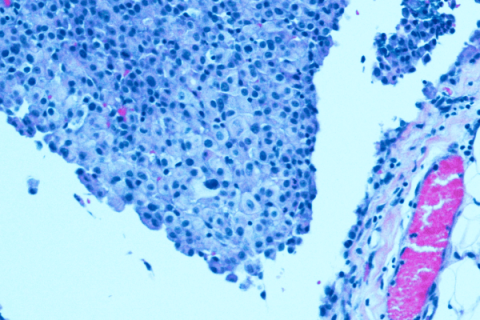

Mesothelioma cells

State of Mesothelioma